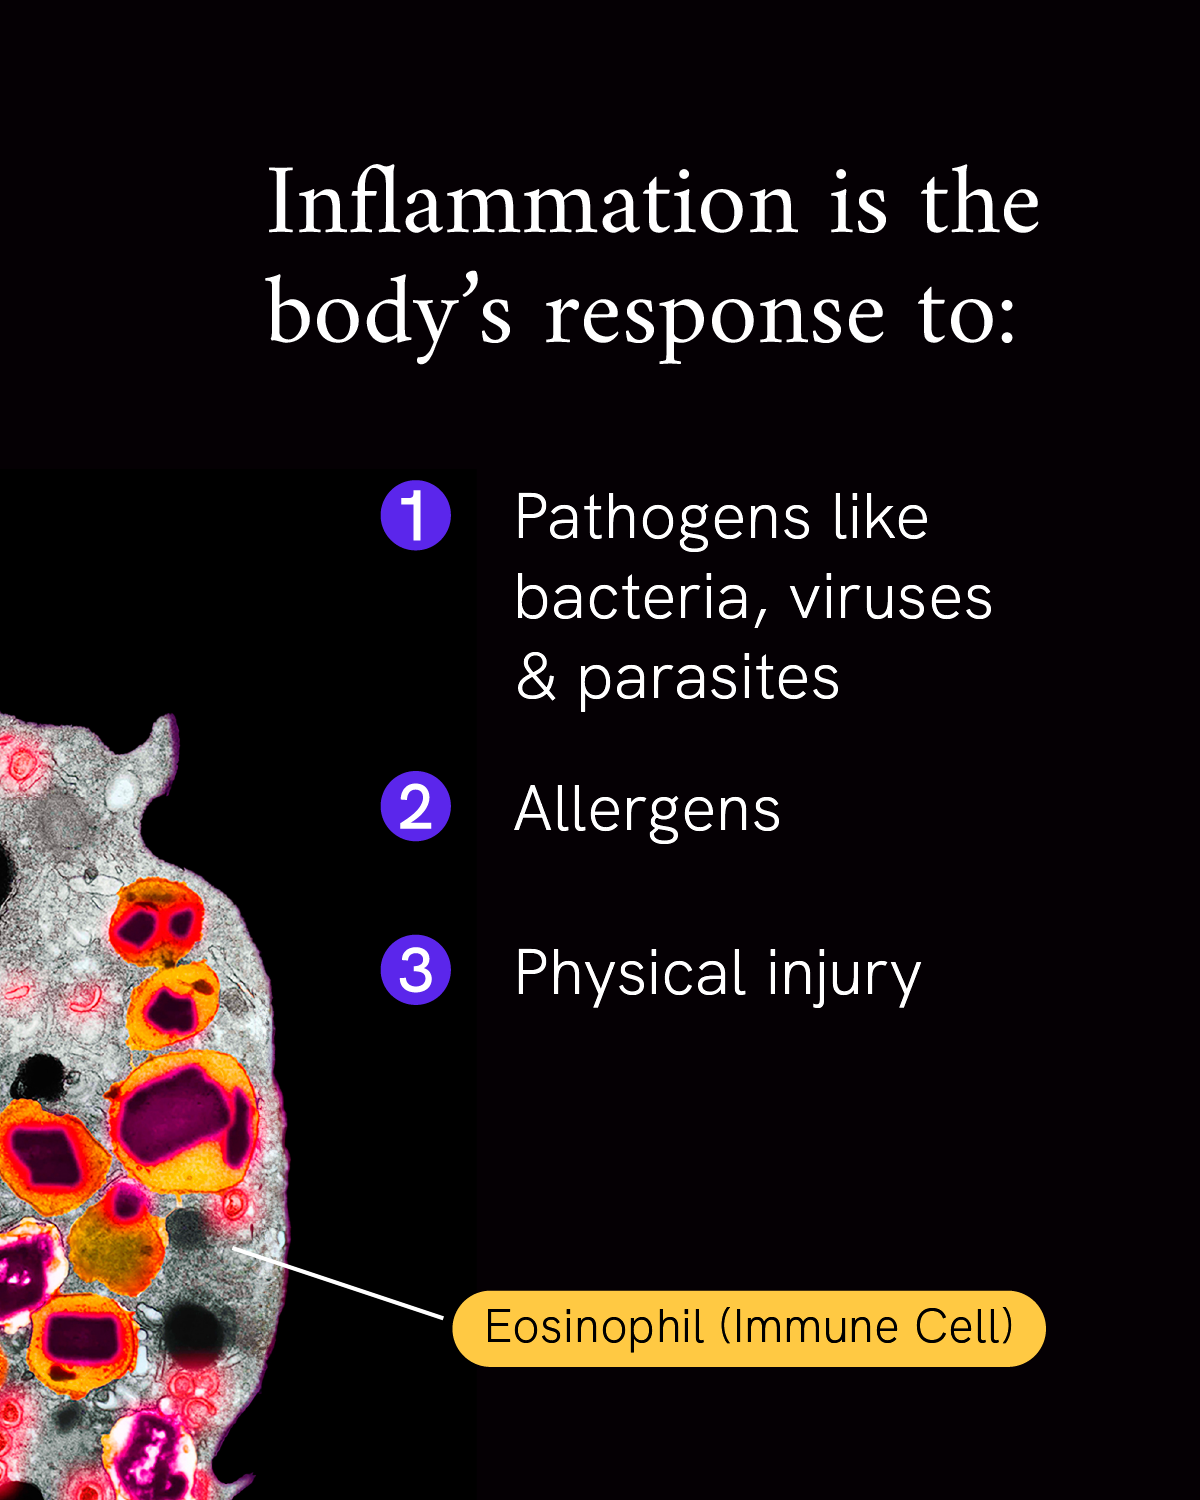

Inflammation is our body’s first line of defense against injury or infection by harmful viruses, bacteria or other pathogens. It’s an important response from the immune system to try to minimize injury or infection and begin the healing process, but too much inflammation at the wrong place or time can become a problem.